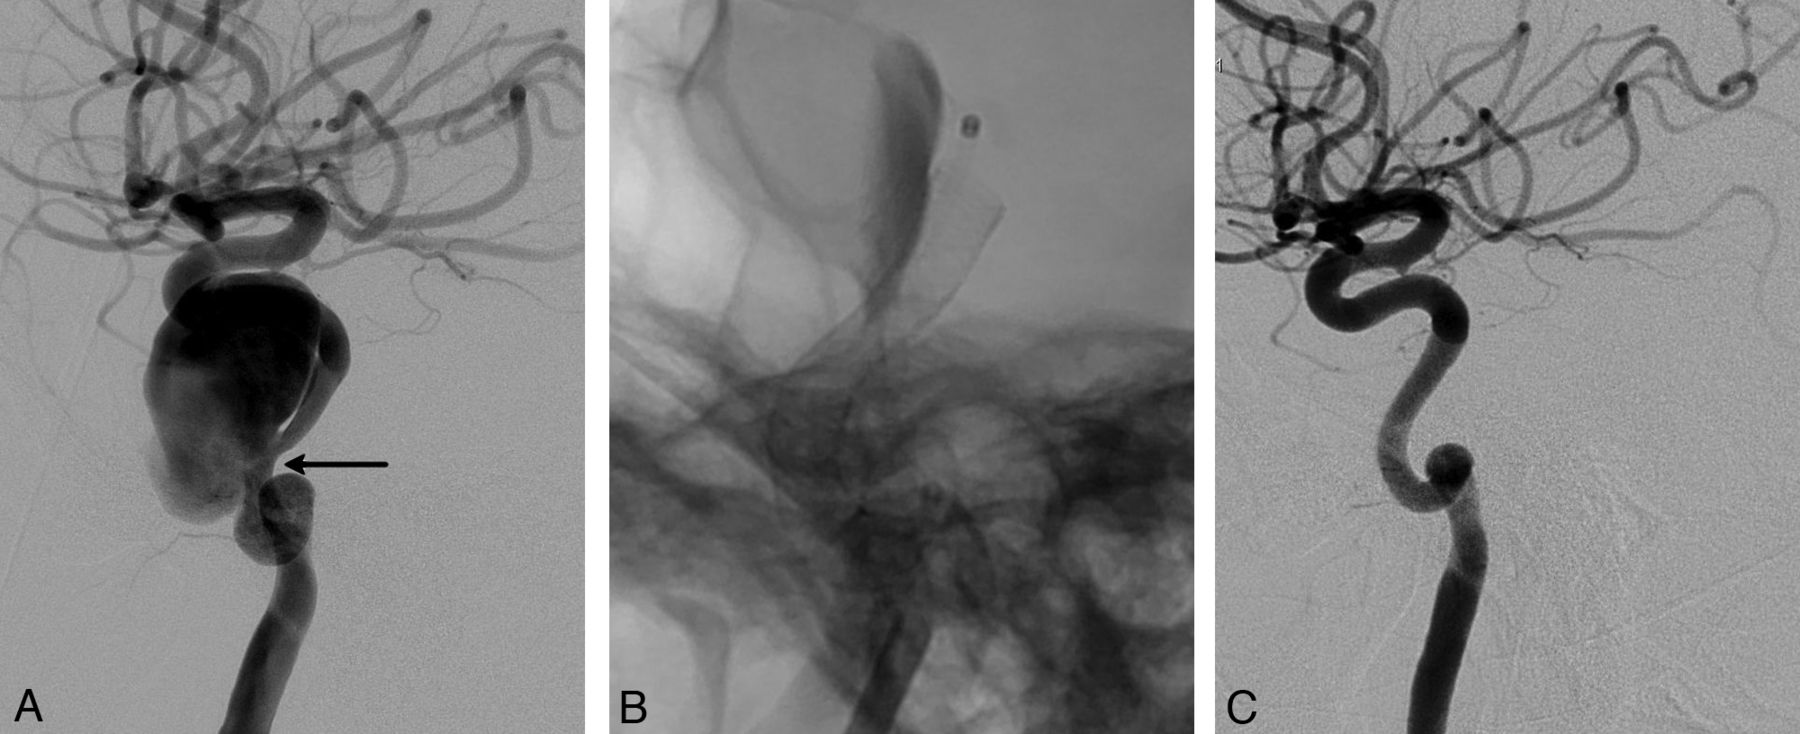

This retrospective study included 251 aneurysms treated with PEDs in 191 consecutive patients (mean age, 49.2 years; age range, 26–71 years; except for 1 pediatric patient who was 13 years of age) between November 2008 and September 2011. One hundred twenty-nine patients were female and 62 were male. Following ethics committee approval, 17 of the patients were included in the Pipeline for Uncoilable or Failed Aneurysms Study. Written informed consent was obtained from each patient. Sidewall aneurysms with wide necks (≥4 mm) or unfavorable dome-neck ratios (≤1.5) (Fig 1), large or giant aneurysms that might have or already had mass effect (Fig 2), fusiform aneurysms (Fig 3), blisterlike aneurysms (Fig 4), recurrent sidewall aneurysms, dissecting aneurysms (Fig 2), aneurysms at difficult angles to the parent artery (so that catheterization of the aneurysm and coiling may have increased risk) (Fig 5), and aneurysms in which a branch was originating directly from the sac (therefore endosaccular obliteration or clipping was likely to compromise the branch or result in a neck remnant) were treated with the PED (Figs 6 and 7). We intended to treat 1 patient with a giant, very wide-neck, cavernous ICA aneurysm presenting with mass effect symptoms by using a PED; however, we failed to bypass the neck of the aneurysm, resulting in treatment of the aneurysm with parent artery occlusion following a balloon occlusion test, without complications. This patient was not included in the study because a PED was not used. This was the only technical failure during the course of the series.

Lateral angiogram shows a giant dissecting ICA aneurysm (A). The intraoperative view demonstrates PEDs (sizes, 4 × 202 and 4.5 × 16 mm) opening to the normal size of the parent artery at the dissected segment (arrow in A) without necessitating balloon angioplasty. Note the contrast stagnation within the sac (B). Six-month control angiography (C) shows total occlusion of the aneurysm and reconstruction of the parent artery.